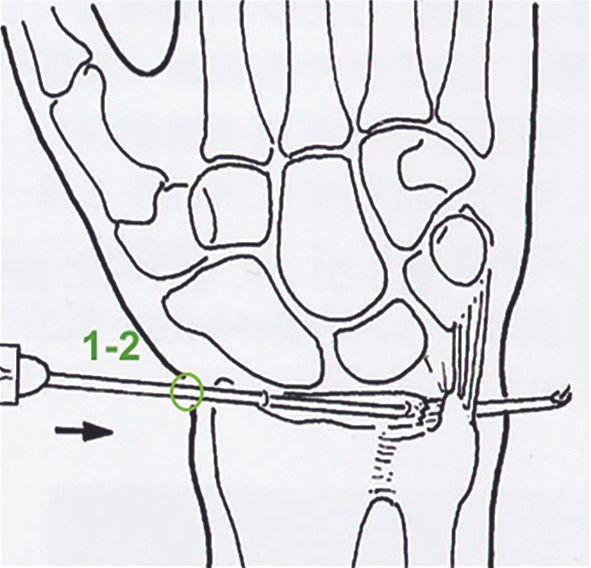

Technique Réinsertion Périfovéale du TFCC sous arthroscopie : Expérience hong-kongaise , Marion Burnier Service de chirurgie de la main et du membre supérieur - Hopital Edouard Herriot, Lyon / , Michael Mak Service de la Main et de Microchirurgie - Prince of Wales Hospital - Hong Kong, China , Wing-Lim Tse Service de la Main et de Microchirurgie - Prince of Wales Hospital - Hong Kong, China , Pak-cheong Ho Service de la Main et de Microchirurgie - Prince of Wales Hospital - Hong Kong, China N°279 - Décembre 2018 ● 9 min de lecture